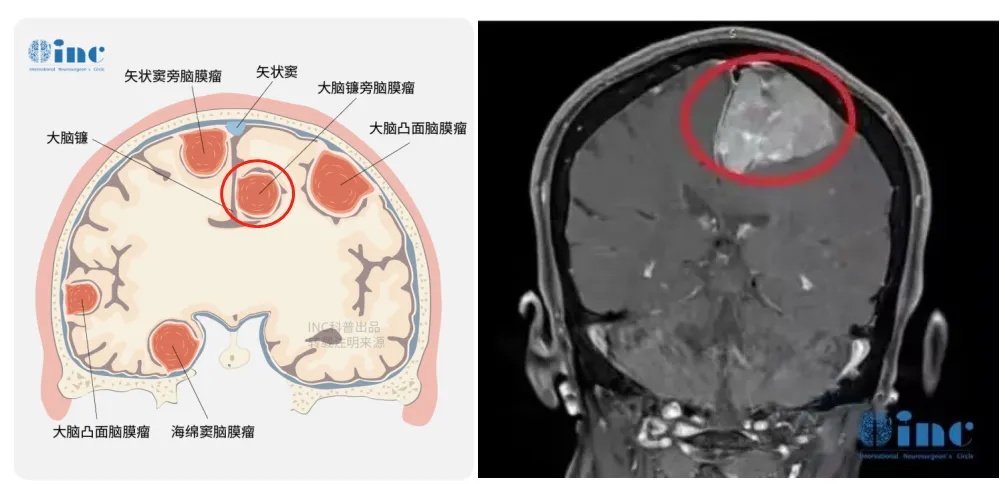

58岁女子头上长了3个“角”?一查竟是多发脑瘤,先切哪个好啊?

医生,我头上这是怎么了?突然起了3个这么大的包? 最近有没有撞到或者受过其他外伤? 没有啊 那先安排做个脑部核磁共振和CT检查看看。 这是一位58岁的女性患者,2021年5月因发现头顶多处...